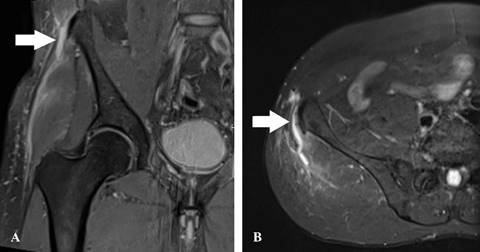

El paciente se había sometido a cirugías por un desgarro del ligamento cruzado anterior en la rodilla derecha hace 27 años y por un desgarro del menisco medial en la rodilla izquierda hace 19 años. Al examen físico, se observó edema leve en la región lateral de la cadera, sin hematomas. Las pruebas de fuerza revelaron dolor en la cadera derecha y disminución de la fuerza en comparación con la cadera izquierda. Los resultados de la resonancia magnética confirmaron un desgarro completo de la inserción proximal de la banda iliotibial (Figura 1).

Figura 1: La imagen de resonancia magnética con supresión espectral de grasa en secuencias ponderadas en densidad protónica (DP) se asentó en: A) la sección coronal y B) la sección axial, demostrando un desgarro completo de la inserción proximal de la banda iliotibial (flecha blanca).